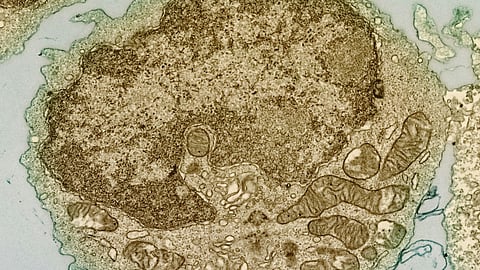

MM is a type of cancer that affects plasma cells in the bone marrow. While standard-of-care treatments like lenalidomide, an immunomodulatory drug (IMiD), have improved survival rates for many MM patients, a significant number still experience relapse due to the development of drug resistance.

ADAR1 inhibits lenalidomide’s activity by editing double-stranded RNA (dsRNA), thus hindering the immune response and reducing the effectiveness of the drug in combating MM growth and proliferation. The researchers discovered that by reducing the levels of ADAR1 and increasing dsRNA accumulation in MM cells, they could increase the sensitivity of the cells to lenalidomide. This would, in turn, lead to the activation of the immune responses and kill the MM cells. The discovery adds a new layer to the understanding of how MM patients may become resistant to IMiD, highlighting the role of dsRNA pathways beyond the previously understood CRBN pathway.